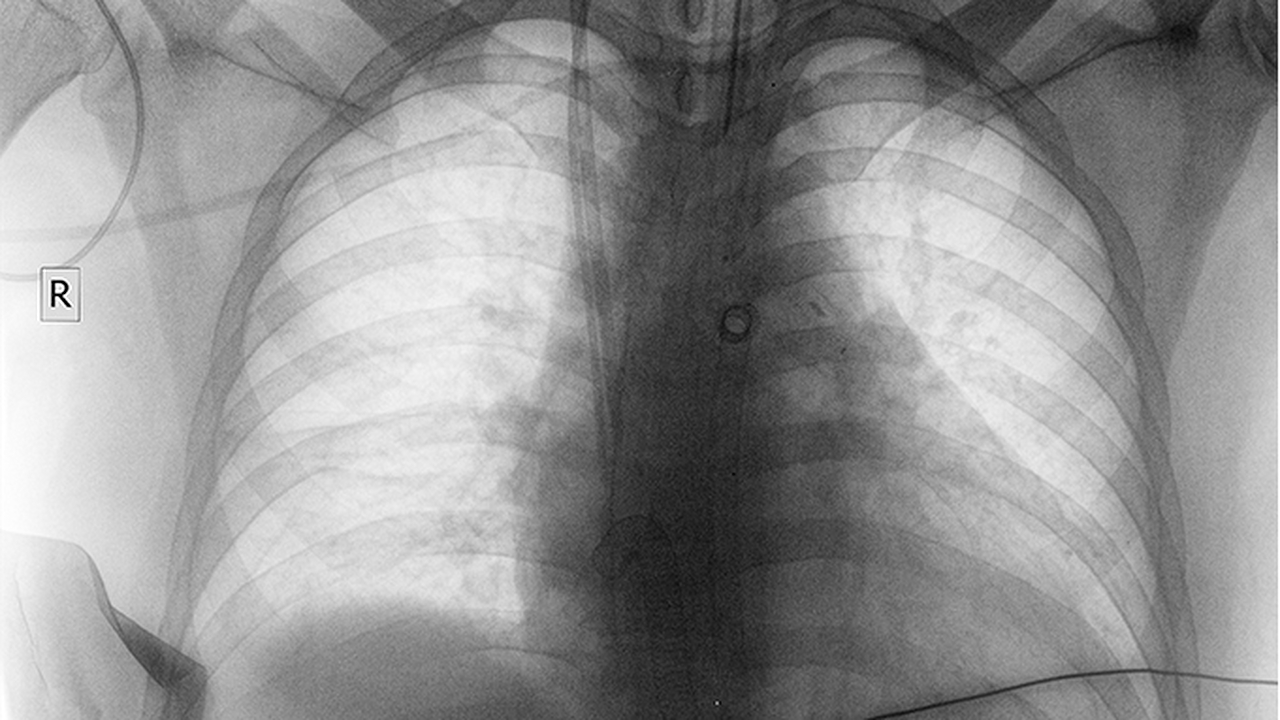

肺癌的發(fā)病原因復雜,主要包括吸煙、空氣污染、職業(yè)暴露、遺傳因素等。早期診斷和規范治療對提高患者生存率至關(guān)重要,因此選擇專(zhuān)業(yè)醫院尤為重要。